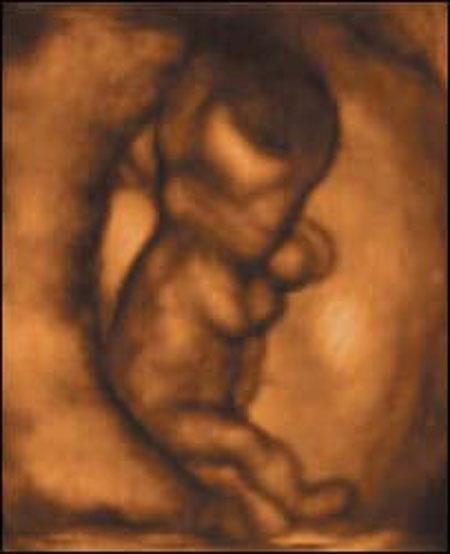

Ультразвуковые съёмки аборта на 12 неделе явно показывают: ребёнок чувствует боль, как любой из нас, и прекрасно понимает, что его хотят убить - он всеми силами старается отодвинуть от себя инструмент и широко раскрывает рот в безмолвном крике, когда у него отрывают сначала ноги, затем часть туловища…

Голову извлекают в последнюю очередь и лицо убитого ребёнка всегда искажено гримасой боли и ужаса. По этим кадрам видно, что практически нет разницы, убить ли 3-месячного ребёнка в утробе или отрезать руки -ноги -голову 5-летнему малышу. Без анестезии и в полном сознании.

- Фильм американского врача Бернарда Нэйтансона, названный «Безмолвный крик», показал всему миру, что такое аборт на сроке 11 недель беременности. Многие врачи и медсестры, посмотрев фильм, прекратили участвовать в абортах.

Это документальный фильм, и авторы рекомендуют соблюдать осторожность при его показе, поскольку некоторые кадры могут вызвать у человека психологический шок: безмолвный крик внутриутробного младенца, искаженное от боли лицо ребенка, погибающего на наших глазах...

Из закадрового текста к фильму: «Инструмент еще не коснулся ребенка, но он уже возбужден, его сердечные удары учащаются и достигают приблизительно 200 ударов в минуту. Вакуум-кюретка нащупывает ребенка, и он широко раскрывает рот в безмолвном крике».